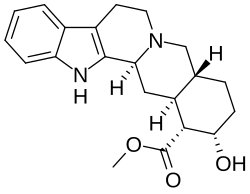

| Yohimbine | Yocon |

|

Blocks α2 receptor, and increases norepinephrine release, thus increasing CNS activity.[2] | Raises blood pressure and heart rate.[2] |

| |